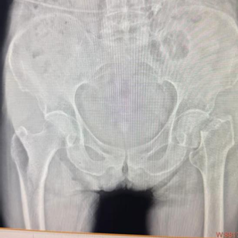

任阿姨 80 岁了,因不慎跌倒导致右侧股骨颈骨折。这种骨折常被称为「人生最后一次骨折」,对高龄患者而言,传统手术创伤大、恢复慢、风险高。如何让老人尽快安全站起,最大程度减少手术创伤与疼痛,是医疗团队面临的核心挑战。经过周密术前讨论与评估,骨科一病区团队在科主任徐明杰的带领下,与田克副主任医师、王延明主治医师共同为患者制定了手术方案,决定采用目前国际先进的 SuperPath 微创髋关节置换技术。该技术源自美国,核心理念在于「微创」与「快速康复」。

在手术团队、麻醉科及手术室的精密配合下,手术历时约一小时顺利完成。术后 X 光片显示假体位置精准,效果理想。